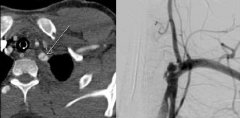

创伤除了全身反应外,主要导致局部实质脏器出血、骨盆骨折出血以及创伤导致的血管损伤出血。血管损伤除了急性出血也导致慢性损伤。创伤后动静脉瘘就是其中之一 男40,近期颈部锐器伤后,2周来左侧颈部进行性肿胀。 增强CT,轴位显示椎动脉与颈内静脉瘘 CT增...